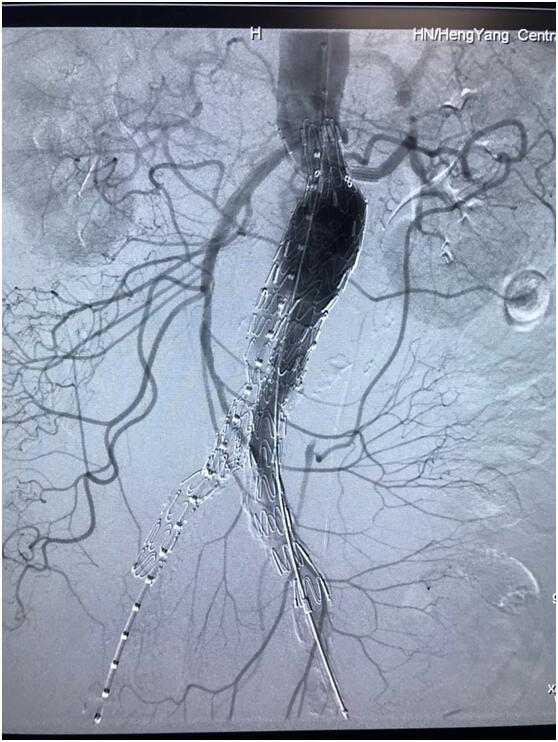

血管介入科行腹主動脈瘤覆膜支架隔絕術(shù)(“褲衩”支架植入)。圖3

患者因腹部搏動性腫塊行成已有4年,伴右下腹疼痛6小時入院,既往有高血壓病史,患者入院后血壓177/96mmHg,醫(yī)護(hù)人員隨即予以控制血壓、止痛處理,CTA檢查提示患者有腎下腹主動脈瘤,合并心 、肝 、肺 、腎等重要臟器疾患,根據(jù) Laplace定律,動脈瘤直徑越大壓力越大,老人動脈脆弱,動脈瘤隨時有破裂的可能性,其危險性大。血管介入科排除各種困難,在麻醉科協(xié)作下行腹主動脈瘤覆膜支架隔絕術(shù)(“褲衩”支架植入),手術(shù)持續(xù)了1個半小時,患者術(shù)后安返病房,麻醉醒后露出了微笑,向醫(yī)務(wù)人員伸出大拇指。